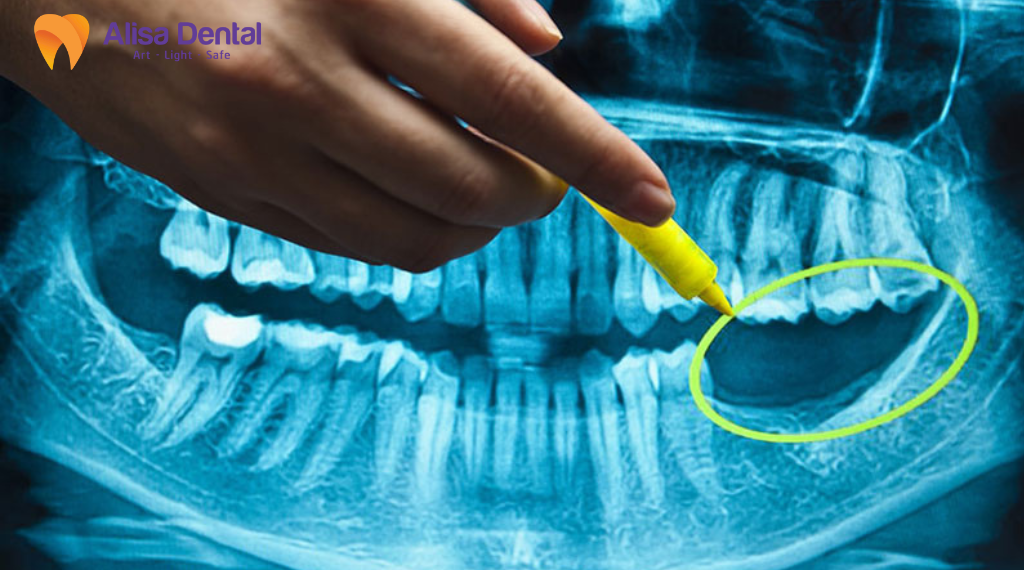

Thăm khám, chụp phim và đánh giá tình trạng sức khoẻ

Bác sĩ kiểm tra răng cần nhổ, mô nướu, khớp cắn và mức tiêu xương tại chỗ. Sau đó, bác sĩ chỉ định chụp X quang hoặc chụp cắt lớp vi tính chùm tia hình nón (CBCT) để xác định thể tích xương, hướng đặt trụ và các cấu trúc giải phẫu liên quan. Với một số ca, bác sĩ yêu cầu thêm xét nghiệm tổng quát để đánh giá khả năng phẫu thuật và lành thương.